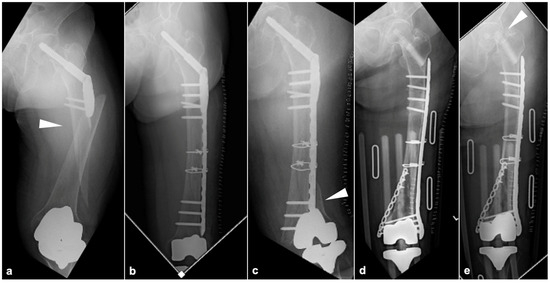

2.3.1. BHA/THA

2.3.3. TKA

3. Results